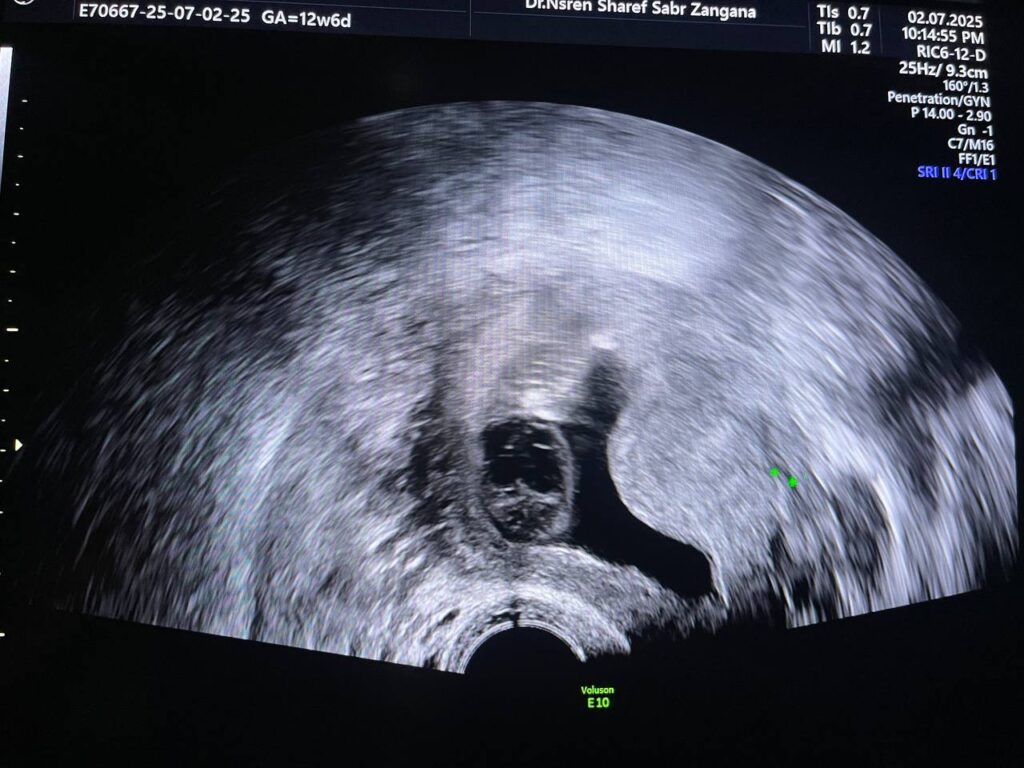

Increase nuchal translucency 7.3mm , mild diffuse skin edema ,Hypoplastic nasal bone, congenital heart disease can not be excluded , please for chromosomal study